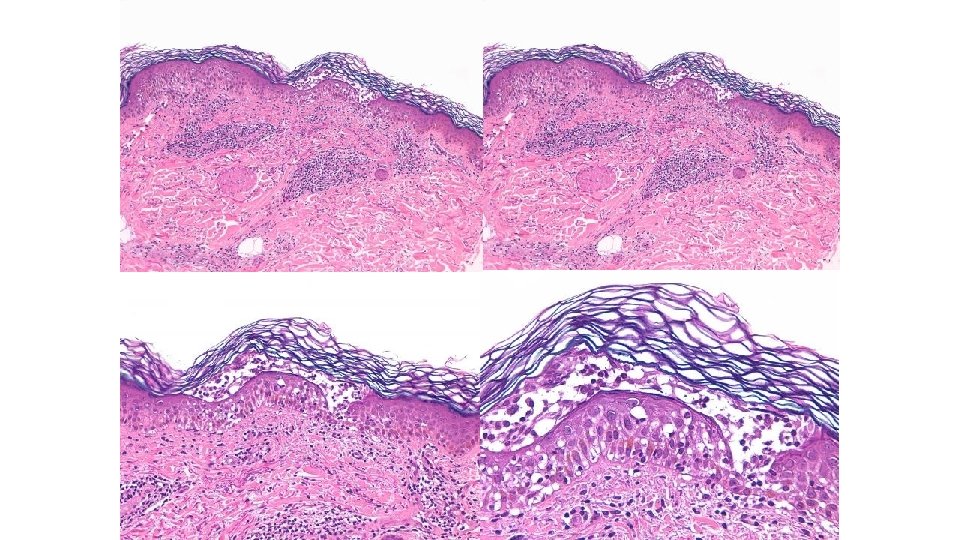

Reacciones liquenoides • Exantema máculo-papular, eritemato-violáceo – Variable: mínimas pápulas descamativas a placas o ampollas – La mucosa oral no se suele afectar • 17% • No influye edad, sexo ni tratamiento previo con ipilimumab • Histología (immunofluorescencia, si vesículas) Hwang SJ et al. J Am Acad Dermatol. 2016; 74: 455

Liquen plano ampolloso

Eccema • 17% • Algunas pueden ser realmente reacciones liquenoides – El estudio histológico podría ser necesario en caso de duda • No aumenta en relación con la edad, el sexo ni el uso previo de ipilimumab Hwang SJ et al. J Am Acad Dermatol. 2016; 74: 455